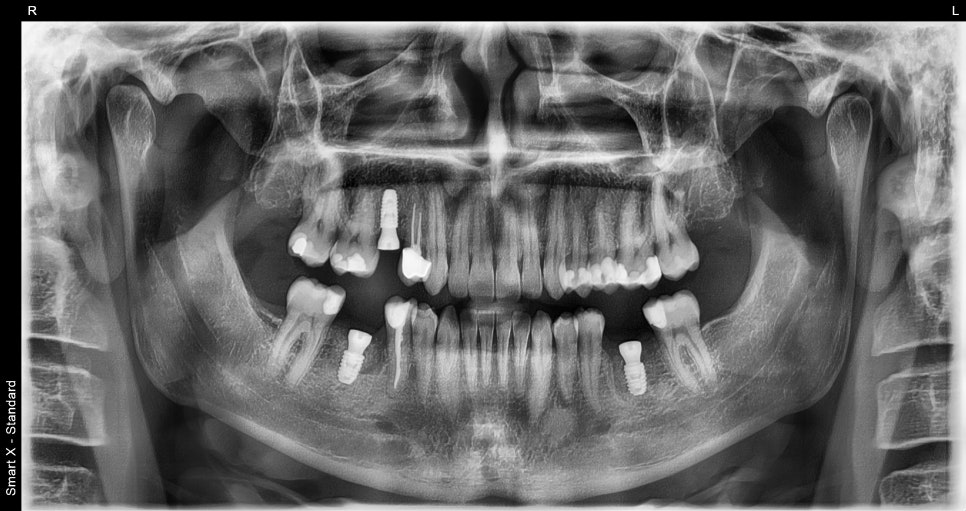

임플란트 식립 후 촬영한 파노라마 엑스레이입니다.

양 옆 치아와 똑같이 가지런히 잘 식립되어 있습니다.

임플란트가 안정적으로 유착된 후, 보철물을 장착 완료 된 최종 파노라마 엑스레이입니다.

임플란트와 크라운 치료 레진 치료 모두 완료된 후의 구강 상태입니다.

기능과 심미성 모두 만족스럽게 회복되었습니다.